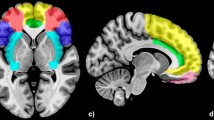

ROIs related to facial emotion

The collection of meta-analysis data using Neurosynth terminated on February 1, 2021. One hundred and 250 studies from the automated meta-analysis survived for the search terms "emotional faces" and "facial expressions", respectively. The brain regions for the search term "emotional faces" included mainly the bilateral AMY, bilateral HIP, and bilateral FFG. The brain regions for the search term "facial expressions" included mainly the bilateral AMY, bilateral HIP, right FFG, left inferior temporal gyrus, right inferior occipital gyrus, right triangular part of the inferior frontal gyrus, right superior temporal gyrus, and right middle temporal gyrus. The ROIs, formed from the area of overlap across the two domains related to facial emotions, included the bilateral AMY, bilateral HIP, right FFG, and right supplementary motor area (SMA). The results are described in detail in Table 2, and an illustration is given in Fig. 2.

The lateral and medial view of brain regions related to both "emotional faces" and "facial expressions" using Neurosynth (p < 0.01, FDR corrected, with a minimum cluster size of 10 voxels). The brain regions associated with FER obtained by using Neurosynth included bilateral AMY, bilateral HIP, right FFG and right SMA. The figure was generated by a brain region visualization tool of "BrainNet Viewer". The color bars showed the correlation between FER ability and brain regions based on meta-analysis. AMY, amygdala; HIP, hippocampus; FFG, fusiform gyrus; SMA, supplementary motor area.